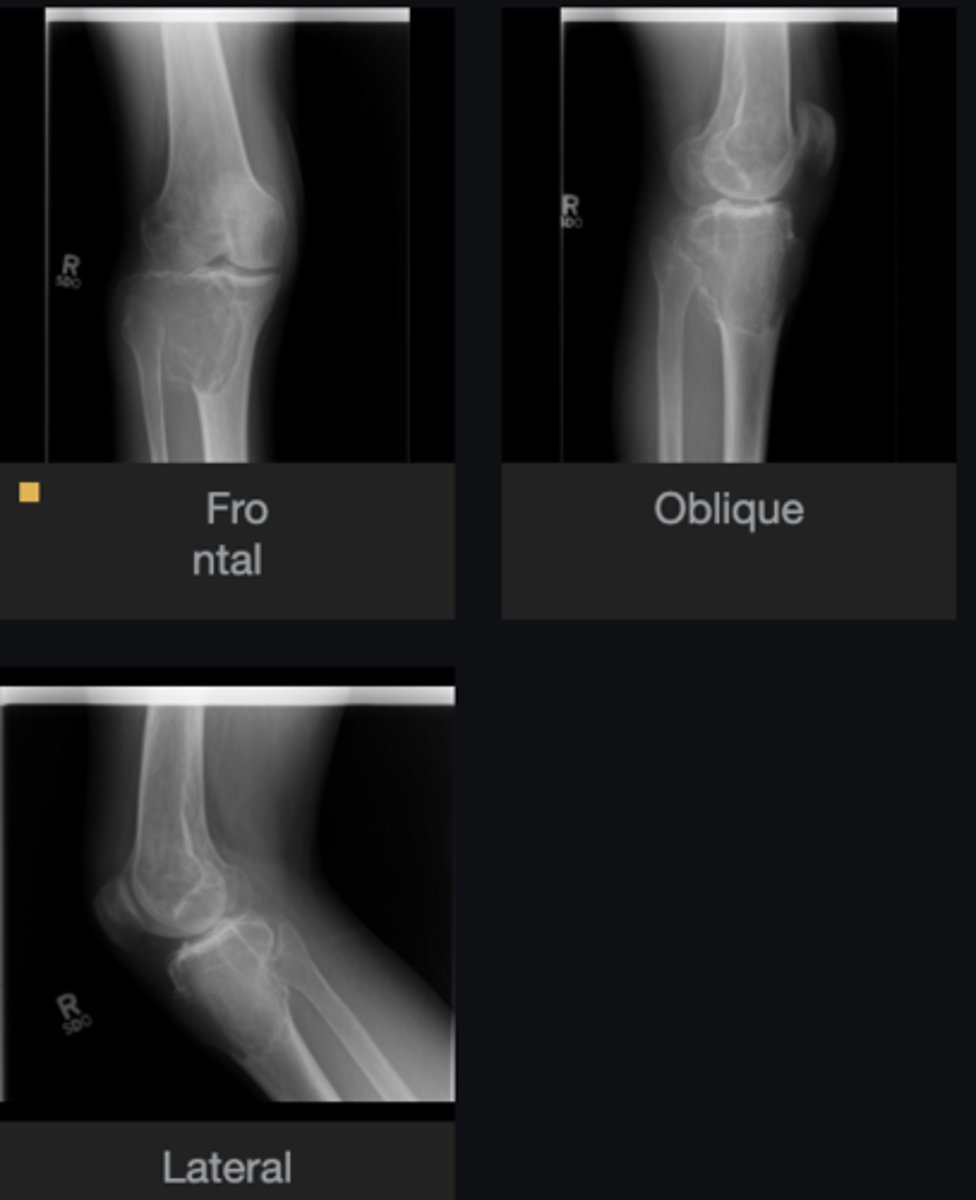

- Solitary

- Eccentric

- Geographic

- Multiloculated

- Fibrous matrix

- Small

- Cortical thinning

- Sclerotic border

Describe the lesion

<p>Describe the lesion</p>

Non-Ossifying Fibroma

Diagnosis?

<p>Diagnosis?</p>

Nothing

Next step?

<p>Next step?</p>